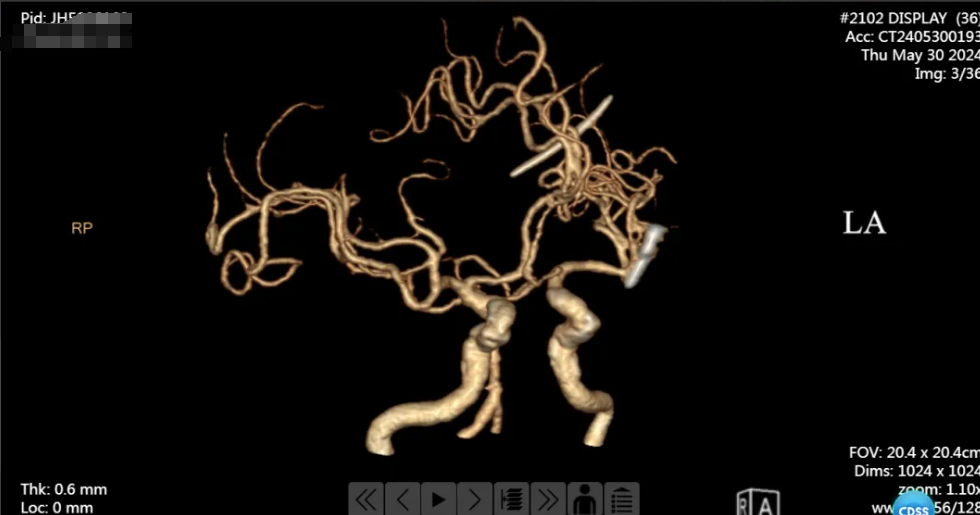

手术很顺利,术后患者安返病房,复查头颅 CT 提示左侧大脑中动脉瘤夹闭完全,载瘤动脉通畅,继续予以对症支持治疗。

我院神经外科团队立即行动,予以对症治疗,同时,在征求患者家属同意后,决定为患者实施开颅动脉瘤夹闭术。时间就是生命,由汤明磊主任主刀,急诊在全麻下行左侧大脑中动脉瘤夹闭术。